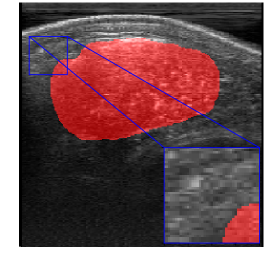

Rib Eye Area (REA). This image dataset consists of ultrasound images of the Longissimus dorsi muscle between the 11th and 13th ribs of cattle. The goal is to automatically calculate the rib eye area (REA), an important region for decision making during cattle breeding. The main challenge is the uncertainty in the REA annotation, since the image is noisy and even experts have difficulty in delimiting the borders of this region. Fig. 3 presents examples of images and the annotation made by a specialist. We can observe that some borders are absent and depend on the subjectivity and knowledge of the annotator. To evaluate the segmentation methods, 76 images with resolution were obtained and labeled by an expert. Due to the number of images, the division of the images in training and testing followed 5-fold cross-validation.

REA dataset. This image dataset has high uncertainty during labeling due to noise from the ultrasound image. In some cases, the border of REA is not completely visible and must be estimated by the specialist. Therefore, the proposed approach becomes essential to obtain accurate segmentation at the edges. The segmentation examples in Fig. 6 show that the baseline was not able to define the REA correctly due to the uncertainty of the labeling. On the other hand, the proposed approach presents results close to the specialist in regions that the border needs to be estimated.